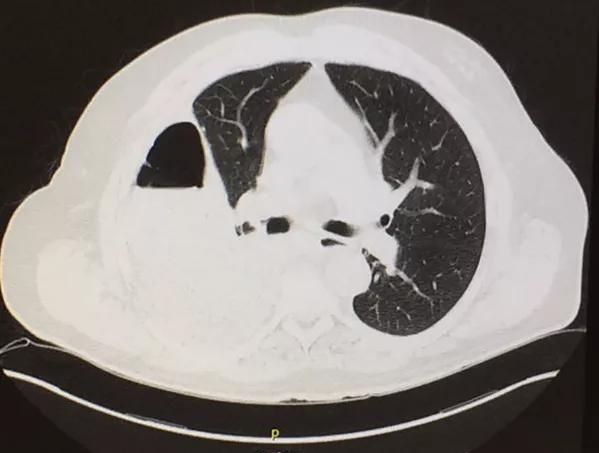

Computed tomography (CT) of the chest at this time showed a small wedge-shaped area of lung consolidation in the right lower lobe (also seen on CT done 1 day before admission to our hospital), with an intrinsic air-fluid level suggesting a focal infarct or lung abscess, now obscured by adjacent consolidation and atelectasis. In the interval since the previous CT, the multiloculated right pleural effusion had increased in size.

Computed tomography shows a wedge-shaped area of low attenuation suggesting a focal infarction in the collapsed and consolidated right lower lobe.